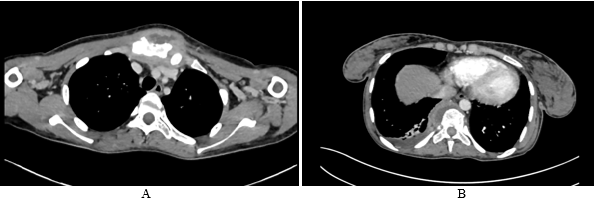

The chest X-Ray showed an enlargement of the middle mediastinum associated to pleural effusion opacity, but any active pulmonary lesions (Figure 1). A computed chest tomography revealed the presence of a parietal mass centered on the sternum, with extension in the soft parts, bone lies of the sternal manubrium, lies of the vertebral hemi-bodies of T10 and T11, cervical lymph nodes, phrenic mediastinal and sub-pectoral nodes with peritoneal and mesenteric involvement (Figure 2). Magnetic resonance imaging of the spine showed tiered thoracic lumbar and sacral spondylitis with paravertebral and anterior epidural collections responsible for spinal cord compression next D10 without signs of spinal cord pain (Figure 3).

Figure 3 Magnetic resonance imaging scans in sagittal section showing multiple round ring signal shadows A- Vertebral body signal abnormalities extending to the posterior arches in hyposignal hypersignal T2 and FATSAT, enhancing after injection of Gadolinium B- tiered thoracic lumbar and sacral spondylitis with paravertebral and anterior epidural collections responsible for spinal cord compression next D10 without signs of spinal cord pain.